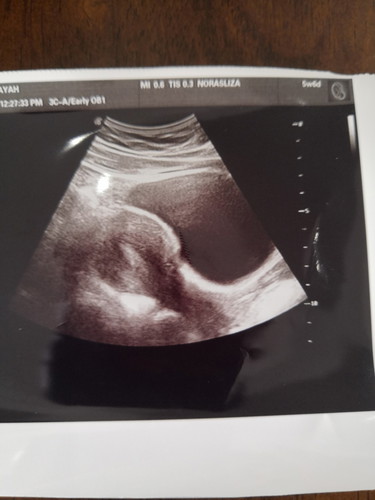

Esok saya masuk 6 minggu.. Tadi pagi masa buang air kecil.. Ada darah keluar.. Saya pergi klinik.. Dr scan tak nampk apa².. Siapa ada pengalaman pendarahan.. Selalunya darahnya mcm mana..?